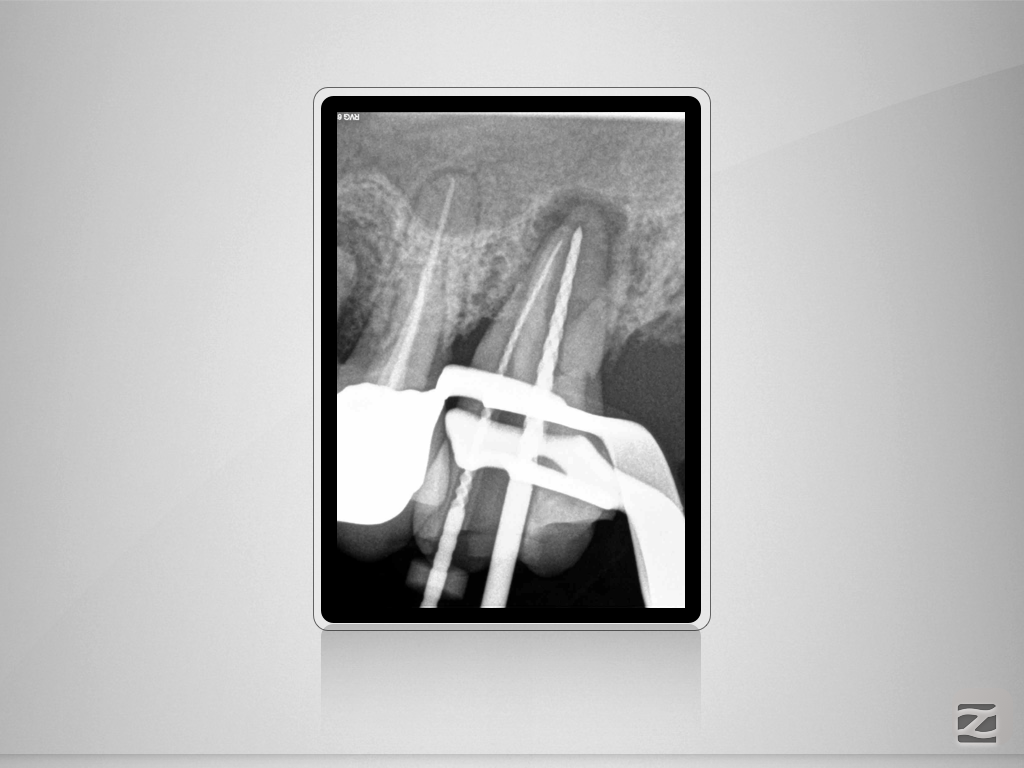

27D.005

Vorher/Nachher – Die Auflösung